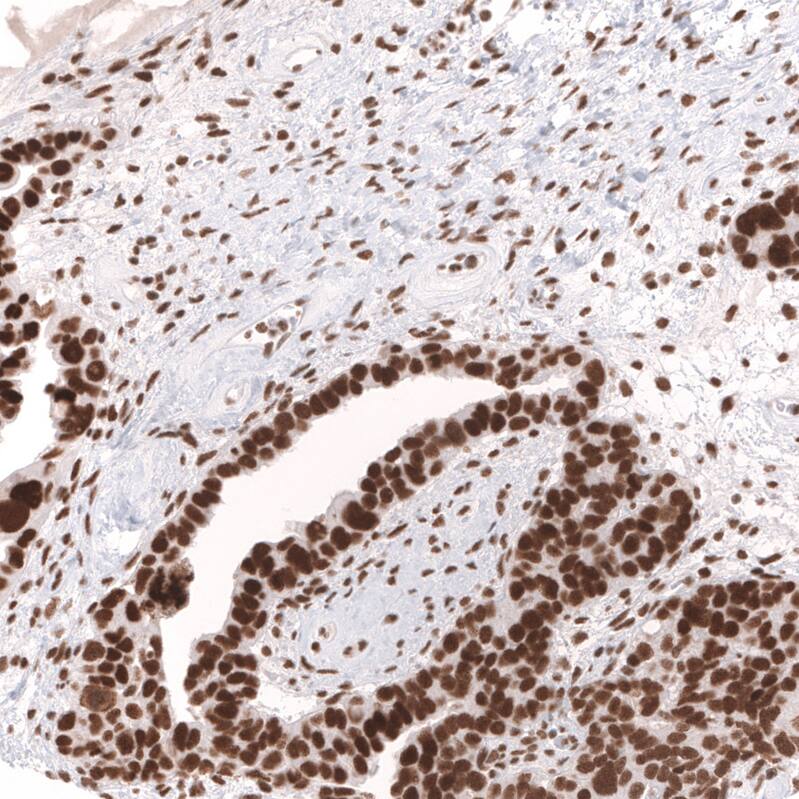

Immunohistochemistry-Paraffin: SNF5 Antibody (CL14031) [NBP3-24595]

Staining of human ovarian cancer (papillary carcinoma) shows strong nuclear positivity in tumor cells.